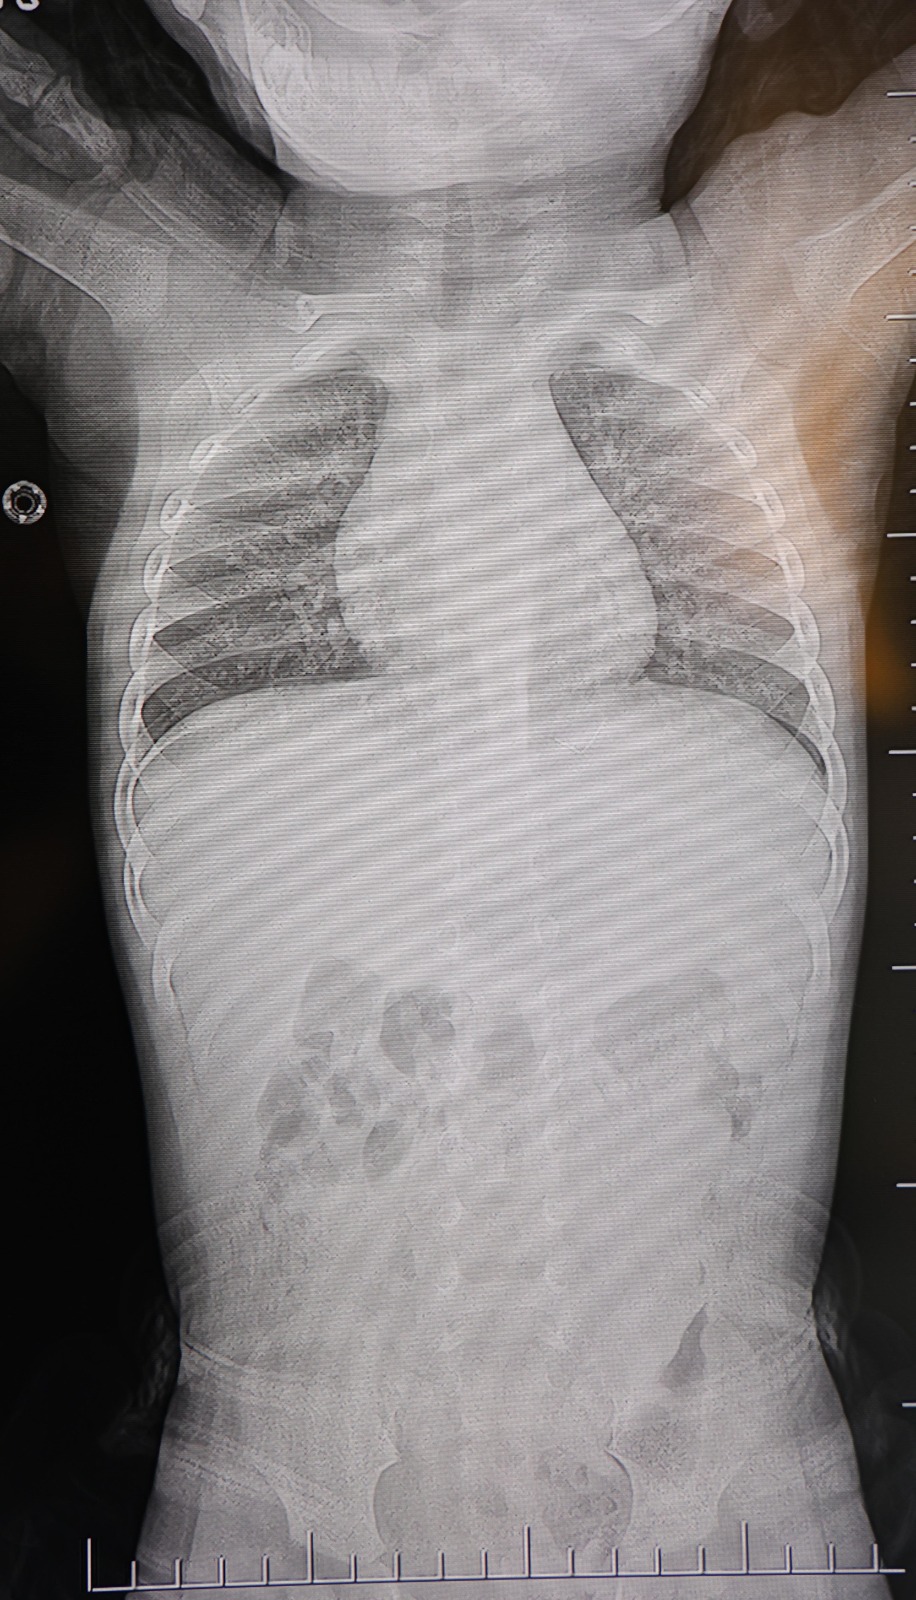

HG Hospital Beyin ve Sinir Cerrahisi Uzmanı Prof. Dr. İdris Altun tarafından yapılan tetkiklerde, yabancı cismin cilt altında, omurilik kanalına yakın bir bölgede olduğu ve akciğer zarına doğru ilerlediği belirlendi. Hasta, genel anesteziye alınmadan, lokal anestezi ve sedasyon eşliğinde ameliyata alındı. Yapılan müdahalede yabancı cisim tamamen çıkarıldı. Çıkarılan cismin, ince zımba teline benzer metal bir tel olduğu ve yaklaşık 2 santimetre uzunluğunda bulunduğu tespit edildi. Hasta, aynı gün taburcu edildi.

"Sırtında yabancı bir cisim olduğu söylenmiş ancak çıkarılamayacağı ve 8 yaşına kadar beklenmesi gerektiği ifade edilmişti. Bize başvurduğunda yaptığımız tetkiklerde, cilt altında, omurilik kanalına çok yakın ve akciğer zarına doğru ilerleyen bir yabancı cisim tespit ettik.

Hastamızı tamamen uyutmadan, lokal anestezi ve sedasyon eşliğinde müdahale ederek lezyonu tamamen çıkardık. Çıkardığımız cismin ince zımba teline benzer, yaklaşık 2 santimetre uzunluğunda metal bir tel olduğunu gördük. Bu yabancı cisim alınmasaydı, bölgede enfeksiyon gelişebilirdi.